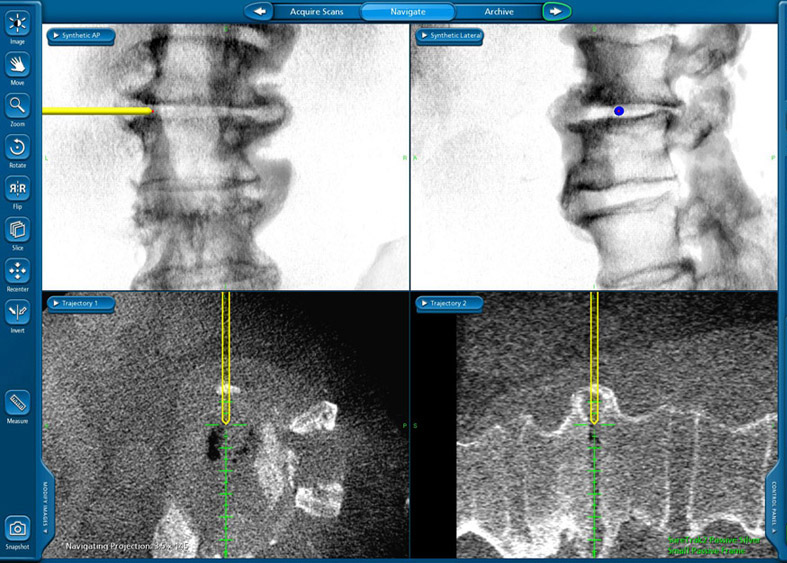

Radiographic navigation allows the operation to be performed with more precision.